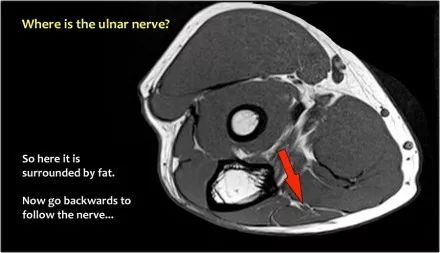

因此,当我们回到图像时,您会发现很难找到神经。任何这些皮下结构都可以是转位神经。一种方法是远端跟随结构,直到你发现远端的尺神经位于由脂肪包围的前臂近端的正常位置。然后当你向近端跟随它时,你会发现这是皮下移位。

在这种情况下,有神经炎。神经增大。在T2W图像上有高信号。另一个标志是在矢状图像(箭头)上看到的束的不均匀扩大。